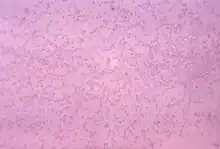

| Gram-stained photomicrograph depicting numerous Pasteurella multocida bacteria | |

Pasteurella multocida is a Gram-negative, nonmotile, penicillin-sensitive coccobacillus of the family Pasteurellaceae.[1] Strains of the species are currently classified into five serogroups (A, B, D, E, F) based on capsular composition and 16 somatic serovars (1–16). P. multocida is the cause of a range of diseases in mammals and birds, including fowl cholera in poultry, atrophic rhinitis in pigs, and bovine hemorrhagic septicemia in cattle and buffalo. It can also cause a zoonotic infection in humans, which typically is a result of bites or scratches from domestic pets. Many mammals (including domestic cats and dogs) and birds harbor it as part of their normal respiratory microbiota.